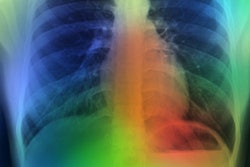

Riverain will highlight the partnerships complementing its ClearRead suite of applications, which help detect disease using patented vessel CT and bone x-ray suppression technology in thoracic images, including expanded relationships with Aidoc, Imbio, and Volpara Health and enhanced collaborations with PACS vendors like Sectra and Nuance.